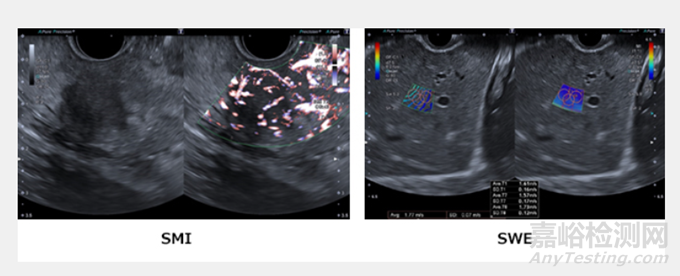

SMI(超微血管成像)技術(shù):佳能醫(yī)療的專有技術(shù),是一種可捕捉微小且緩慢的血流的血流成像技術(shù)。彩色多普勒 可視化低速血流,具有高靈敏度、高分辨率、高幀率和低偽影。

SWE(剪切波彈性成像)技術(shù):當(dāng)使用EUS診斷病變的炎癥程度以及良惡性時,有關(guān)病變組織硬度的信息是一個重要的標(biāo)準(zhǔn)。

SWE(剪切波彈性成像)是一種以數(shù)值和彩色圖顯示組織硬度的技術(shù),使得更客觀地評估硬度成為可能。